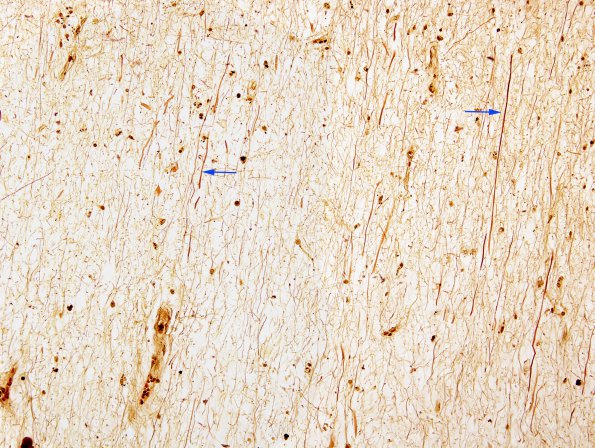

Closeup of the chronic demyelinated inactive focus shows a large amount of axon loss, although long stretches of residual axons (arrows) are seen (Bielschowsky silver stain)